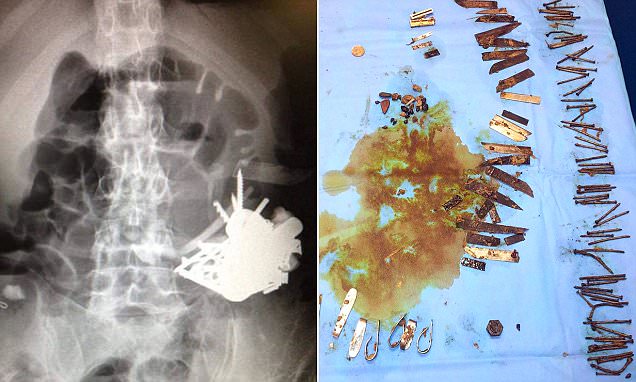

52‑летний мужчина в течение пяти лет пять раз ложился под нож из‑за плотного комка из мелких металлических предметов, который образовывался в его желудке.